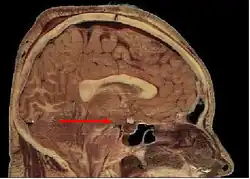

Местоположение гипоталамуса в мозге

Гипоталамус является частью промежуточного мозга. Он образует основание и стенки нижней части третьего желудочка. Название своё он получил от греч. гипо- (под, внизу) и таламос (чертог, спальня), так как он располагается под таламусом. Гипоталамус отделён от таламуса гипоталамической бороздой (лат. sulcus hypothalamicus). Анатомические границы гипоталамуса определены недостаточно чётко, что связано с тем, что некоторые группы клеток заходят в соседние области, а также с некоторой неопределённостью в терминологии[3]. Считается, что спереди (рострально) гипоталамус ограничен терминальной пластинкой (лат. lamina terminalis), а его задняя (каудальная) граница — воображаемая линия от задней комиссуры (лат. commissura posterior) до каудальной поверхности сосцевидных тел. Дорсолатерально гипоталамус доходит до медиального края мозолистого тела[4].

В нижней части гипоталамуса выделяются такие структуры, как сосцевидные тела (лат. corpus mamillare), серый бугор (лат. tuber cinereum) и воронка (лат. infundibulum). Воронка отходит от серого бугра, средняя часть воронки приподнята и называется срединным возвышением (лат. eminentia mediana), которое в некоторых классификациях относят к серому бугру, а в некоторых — к нейрогипофизу[5]. Срединное возвышение содержит кровеносные сосуды, переносящие выделяемые гипоталамусом вещества в гипофиз. Нижняя часть воронки переходит в ножку гипофиза.